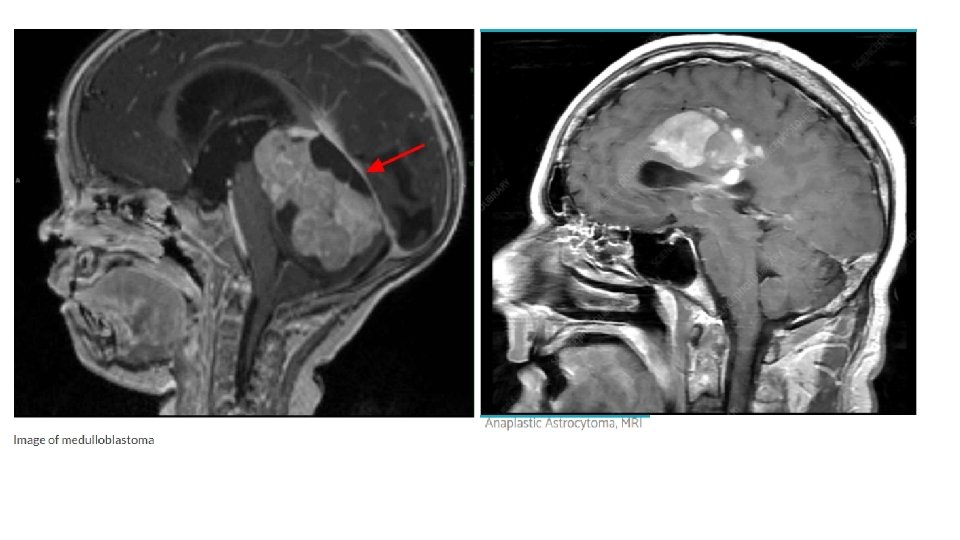

Central Nervous System Tumors • CNS tumors are the most common solid tumors in children • Most central nervous system (CNS) tumors in children are primary tumors: low-grade astrocytomas or embryonic neoplasms (medulloblastoma, ependymoma, germ cell tumor). • Incidence is approximately 33 cases per 1 million children under 15 years of age. • The incidence peaks before age 10 years • Most CNS tumors etiology is unknown • certain inherited syndromes increase risk of CNS tumors including NF (types 1 and 2), Li-Fraumeni syndrome, and von Hippel-Lindau syndrome,

Laboratory/Imaging Studies • Magnetic resonance imaging (MRI) brain and spine is currently the examination of choice • CSF histologic testing is essential to determine the presence of metastatic disease • LP is contraindicated in presence of increased ICP